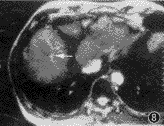

各个序列的病变检出率详见表2。对于囊性病变(肝囊肿与海绵状血管瘤),除epi外其他各序列间的检出率无明显差异(χ2=4.739,P>0.05)。各序列均检出所有大于5 cm的实性病变,但EPI序列的病灶与肝实质对比高于true-FISP、HASTE及TSE。直径2~5 cm的实性病变,IR-EPI-ld序列的检出率高于true-FISP(χ2=6.081,P<0.05)和TSE(χ2=3.888,P<0.05),略高于HASTE但无统计学差异(χ2=2.867,P>0.05)。对于直径小于2 cm的实性病灶,IR-EPI-ld序列的检出率明显高于true-FISP(χ2=23.76,P<0.001)、HASTE(χ2=11.85,P<0.001)及TSE(χ2=14.26,P<0.001)(图1~7)。1例肝硬化增生结节癌变,IR-EPI-ld T2WI清楚显示了结节内的癌变灶(图8~10)。在带有低度扩散梯度场的IR-EPI-ld与EPI-ld T2WI图像中,血管断面呈明显低信号,容易与小病灶区分(图11,12)。

图4~7 男,62岁,乙型肝炎肝硬化,右肝后叶小肝癌。图4为true-FISP T2WI,图5为HASTE T2WI,除显示肝实质信号不均匀外,两个序列均未能显示局灶性病变;图6为IR-EPI-ld T2WI,右肝后叶见一直径1.8 cm的高信号结节;图7为动态增强扫描动脉期,病灶明显强化